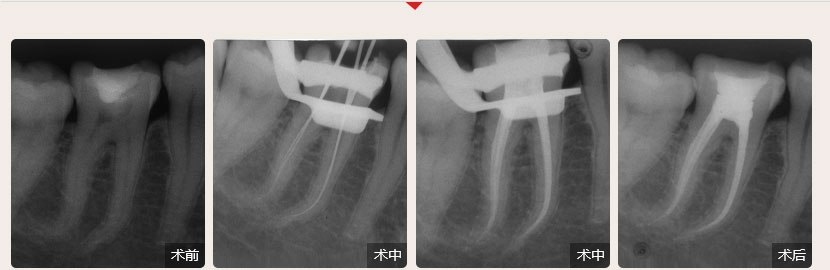

德倫口腔醫(yī)生全國(guó)根管治療技術(shù)競(jìng)賽獲獎(jiǎng)案例展示